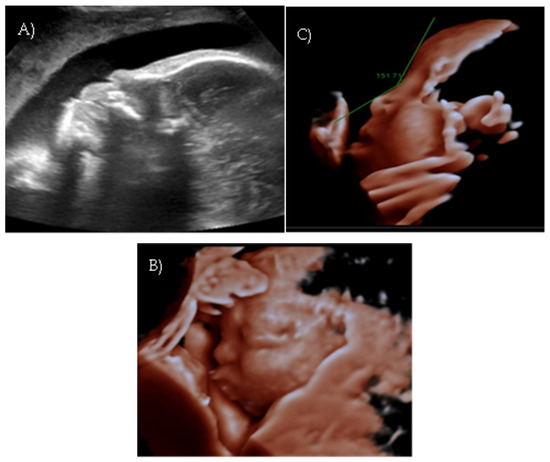

A targeted second-level ultrasound at our center revealed a flat fetal facial profile: the nasal-frontal angle measured 151.50°, and flattening of the curvature of the maxillary alveolar processes was noted (Width: 26.44 mm, Cut-off at 21 weeks: 23.1 mm [6]) suggestive of Binder-type maxillonasal dysplasia, moderate monolateral calyceal-pelvic dilatation of 8 mm in the left kidney, two echogenic intracardiac foci, and long bone biometry at the lower limits of normal (Figure 3 A–C).

Polyhydramnios developed; a flat fetal facial profile with mild verticalization of the nasal bone (Nasal-frontal angle: 151.71°, cut-off: <143°) and slight prognathism were noted (Figure 4A–C).

Figure 3. Case 3. (A) Flat fetal profile, 3D reconstruction. (B) Nasal-frontal angle: 151.50°. (C) Flattening of the curvature of the maxillary alveolar processes. Width: 26.44 mm.

Figure 4. Case 4. (A) Flat fetal profile. (B) 3D reconstruction of the facial profile. (C) Nasal-frontal angle: 151.71°.